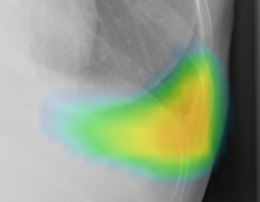

(2)ヒートマップ/輪郭表示機能

異常所見の存在可能性(確信度)を、青から赤へのグラデーションで示すヒートマップ表示について、多くの利用者から好評との声をもらっている。一方、モノクロモニタを利用する一部の読影環境では、淡いヒートマップが確認しにくいという課題があった。新バージョンでは、異常所見の疑われる領域の表示方法として、「ヒートマップ表示」「輪郭表示」「ヒートマップと輪郭の併用表示」の3つの表示パターンが選択可能になった。これにより、各施設の運用環境に応じた最適な表示方法を利用できる。